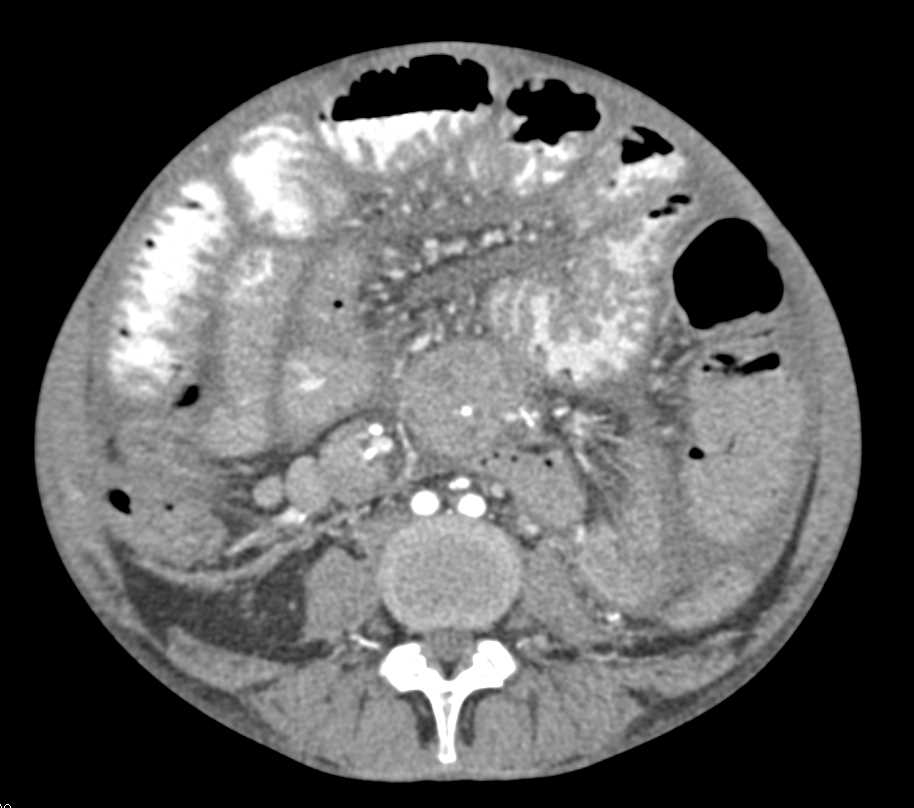

GSW with Renal and Duodenal Injury with Active Bleed Defined